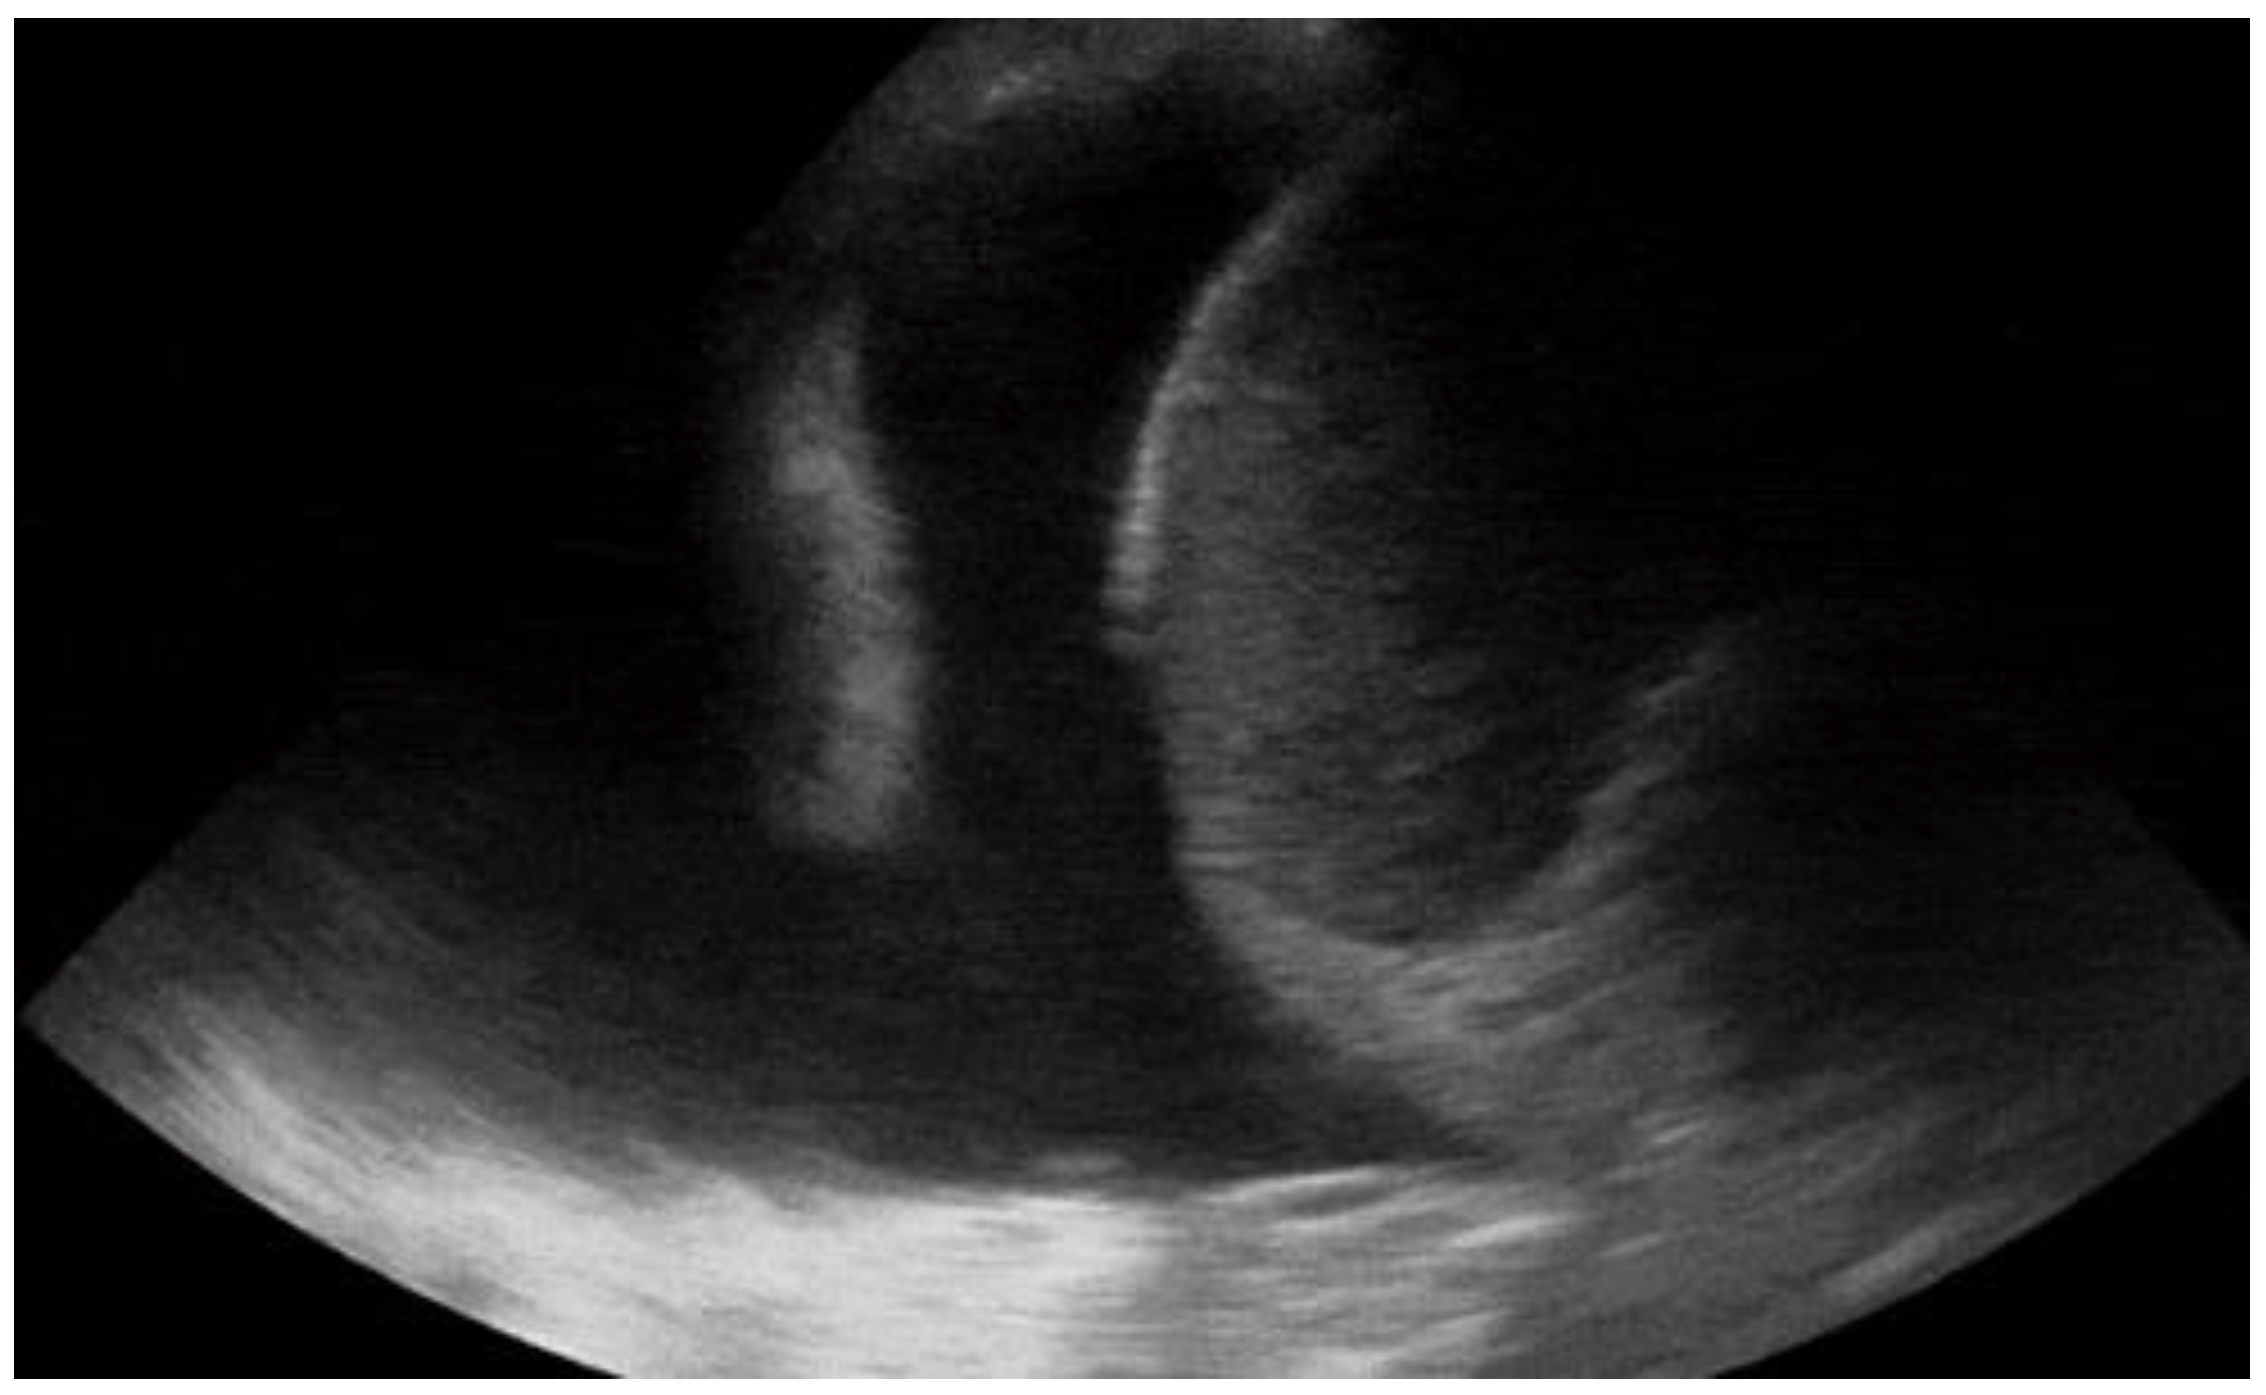

| Pleural effusion | Detection of hypoechoic material in the pleural cavity (Figure 7) |